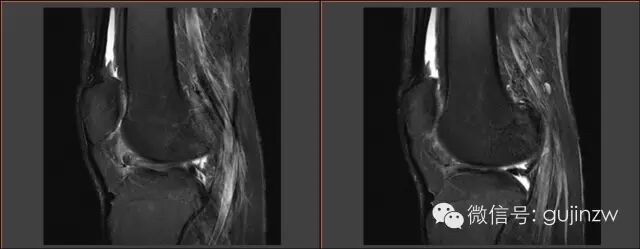

MRI

病例2

• 男,24岁。

• 主诉:打羽毛球扭伤致右膝关节疼痛活动受限1天。

• 症状:右膝关节疼痛,活动受限,交锁,伴弹响。

• 体征:膝关节活动度:15-120度,浮髌试验弱阴性,内外侧关节间隙无压痛。

• 被动挤压:麦氏征(+),Apley征(+)。

• 主动挤压:Ege‘s征(+),Thessaly 20°征(+)。